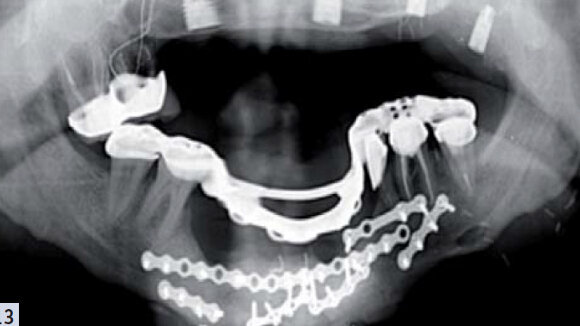

Étienne Waltmann de la faculté de Strasbourg abordera ce troisième chapitre de la séance. Il est co-auteur notamment de « Implants et prothèse partielle amovible », édité en 2010. Ses activités cliniques et pédagogiques s’effectuent dans l’unité fonctionnelle de prothèse amovible, centrée sur l’implantologie. Son activité hospitalo-universitaire à temps partiel lui permet d’exercer une activité libérale en cabinet. Le dernier chapitre de cette séance représente la partie « défi » d’une branche de notre profession qu’est la prothèse maxillo-faciale (PMF). Le cas présenté pourrait être un de nos anciens patients, victime d’un accident de la vie, d’un carcinome, ou d’une tentative d’autolyse. Savoir qu’il est possible de lui venir en aide prothétiquement et améliorer sa qualité de vie est déjà un élément de réponse important pour lui et ses proches. C’est Bernard Giumelli qui exposera ce rapport de cas. Praticien et enseignant à la faculté de chirurgie dentaire de Nantes, il a traité et publié de nombreux cas de prothèse maxillo-faciale au sein de son exercice hospitalier.